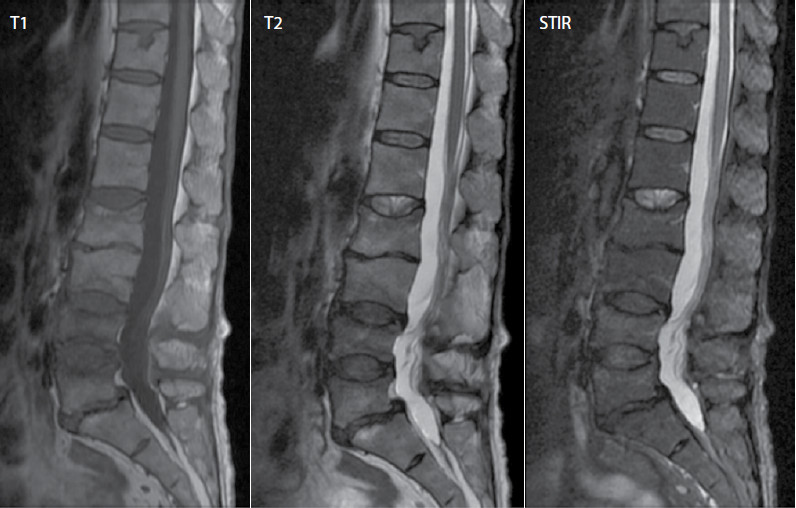

En los paraclínicos iniciales se evidencian fracturas vertebrales por insuficiencia en L2, L4 y L5, en radiografía simple de columna (figura 1), que se caracterizaron con resonancia magnética (figura 2). En el estudio de osteoporosis secundaria, se descarta hiperparatiroidismo, alteración del perfil tiroideo, hepático y renal. No se evidencia pico monoclonal en la electroforesis de proteínas. Se encuentra hipoalbuminemia y perfil fosfocálcico con déficit de vitamina D (tabla). Por lo que se considera osteoporosis secundaria a enfermedad inflamatoria intestinal. Se inicia manejo interdisciplinario con nutrición, terapia física, clínica del dolor y gastroenterología. Se inicia acompañamiento nutricional y rehabilitación física, suplencia de calcio y vitamina D y teriparatida, con mejoría de la sintomatología.

Figura 1. Fractura bicóncava de vértebra L2 con pérdida de aproximadamente 20% de la altura del cuerpo vertebral. Fractura por acuñamiento anterior de vértebras L3, L4 y L5 con pérdida de aproximadamente 10%, 30% y 25% de la altura de los cuerpos vertebrales, respectivamente. Cambios espondilóticos multinivel con formación de osteofitos marginales laterales en la columna lumbar. Cambios por artrosis facetaria y signos de osteocondritis multinivel más prominente en L2-L3. Anterolistesis de L5/S1 grado I por espondilólisis.